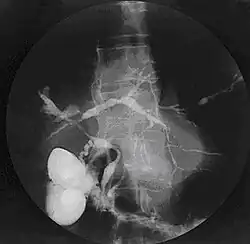

Cholangiogram of primary sclerosing cholangitis

PSC is generally diagnosed on the basis of having at least two of three clinical criteria after secondary causes of sclerosing cholangitis have been ruled out:

• serum alkaline phosphatase (ALP) > 1.5x the upper limit of normal for longer than 6 months

• cholangiography demonstrating biliary strictures or irregularity consistent with PSC

• liver biopsy consistent with PSC (if available)

Historically, a cholangiogram would be obtained via endoscopic retrograde cholangiopancreatography (ERCP), which typically reveals "beading" (alternating strictures and dilation) of the bile ducts inside and/or outside the liver. Currently, the preferred option for diagnostic cholangiography, given its noninvasive yet highly accurate nature, is magnetic resonance cholangiopancreatography (MRCP), a magnetic resonance imaging technique. MRCP has unique strengths, including high spatial resolution, and can even be used to visualize the biliary tract of small animal models of PSC.[22]